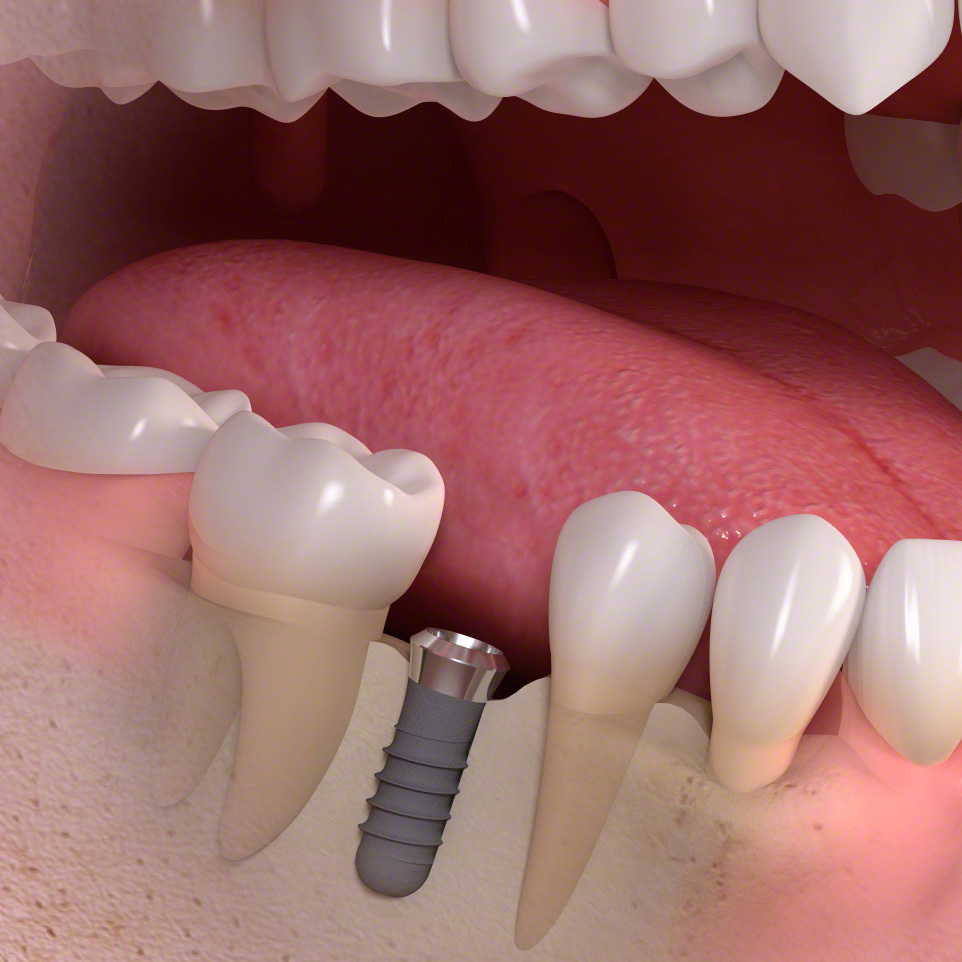

(通常のインプラント法)

歯科インプラントとは、歯を失った部分に人工歯根(主にチタン製)を外科的に埋め込み、その上にセラミックなどで作られた人工の歯を取り付けて、機能と見た目を回復する治療法です。

インプラント (1本欠損ケース)

・健康な歯を削る必要がなく、周りの歯に負担をかけません。

歯を再生する時、インプラントは前後の歯に固定源を求めない唯一の治療法になります。自費治療になります。

インプラント埋め込み

手術で歯肉をめくって骨にインプラントを埋め込みます。治癒期間を待ちます。

インプラント土台接続

手術でインプラントを露出させ、土台を接続します。

セラミックの歯を固定

セラミックの歯を①ネジ止め②接着剤で仮止め、のどちらかで固定します。